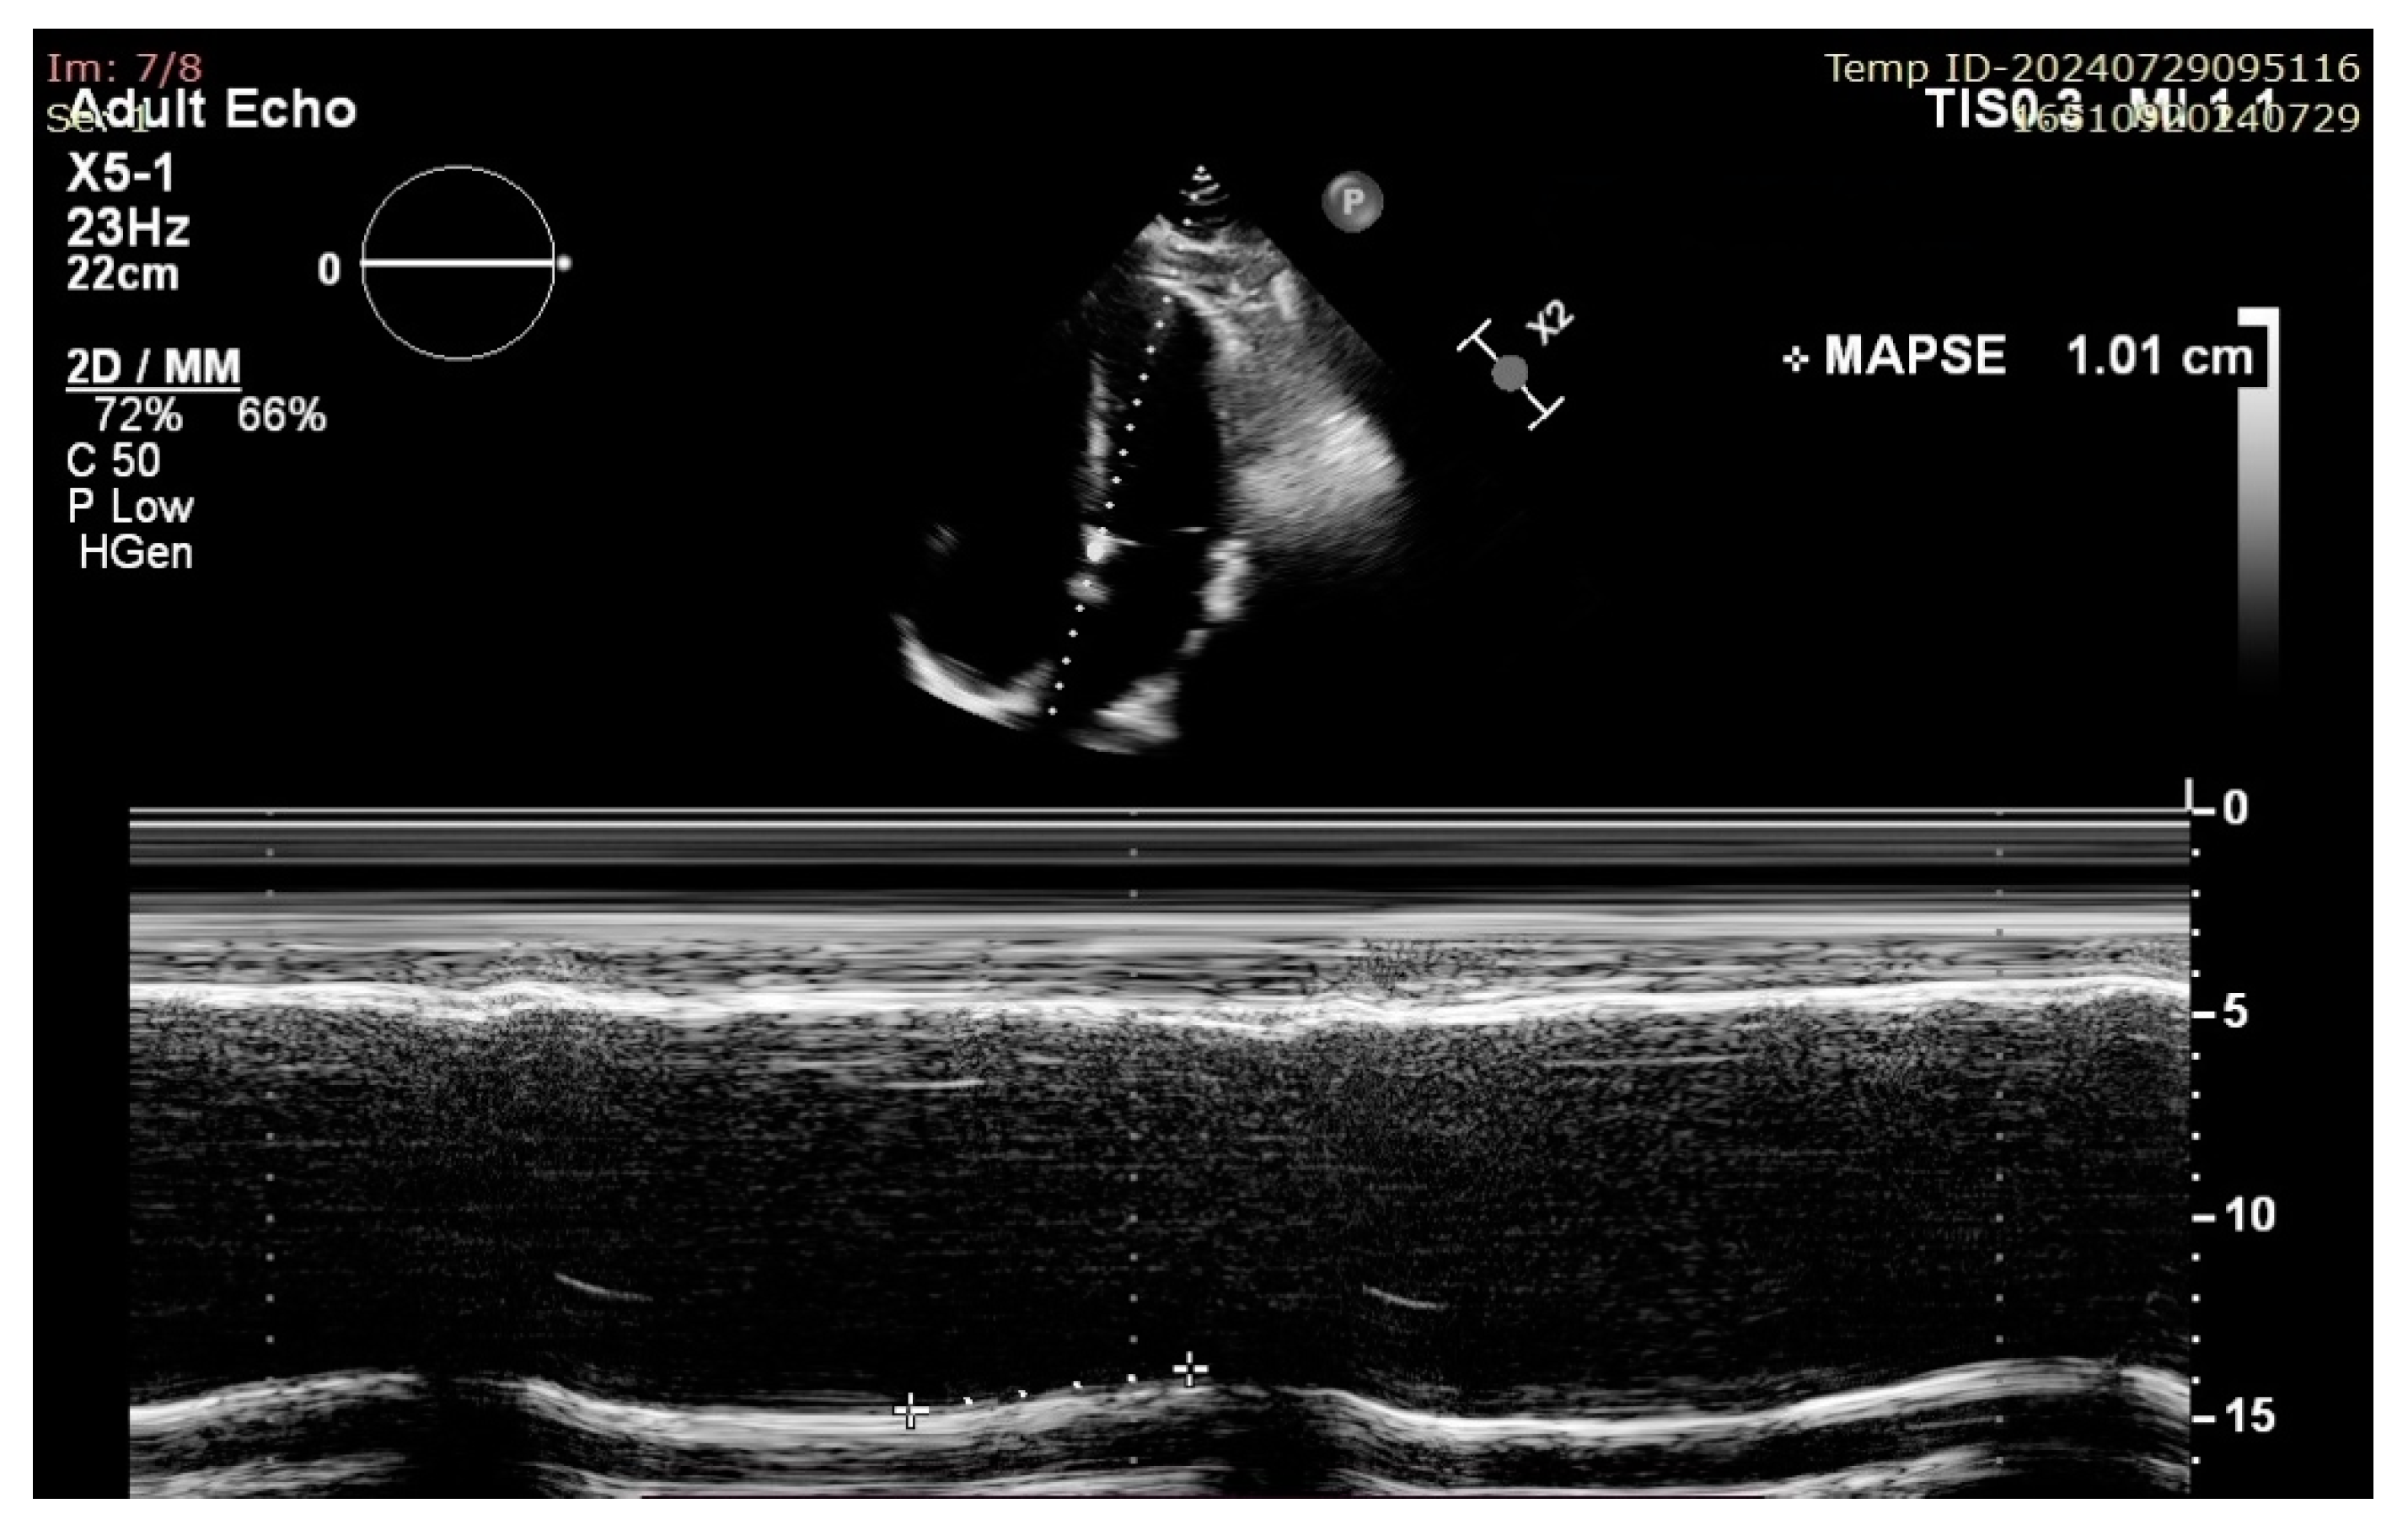

Mitral Annular Plane Systolic Excursion (MAPSE): A Review of a Simple and Forgotten Parameter for Assessing Left Ventricle Function